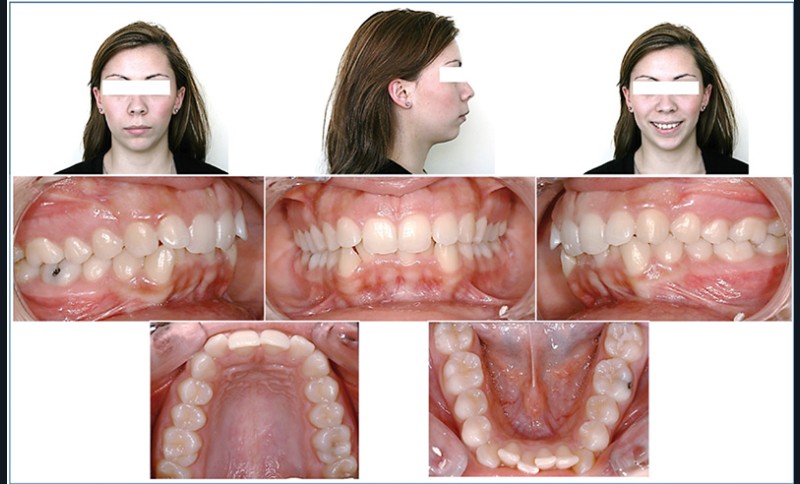

À l’examen exobuccal, le visage est ovalaire, les étages de la face sont équilibrés. Le profil général est convexe avec un sillon labio mentonnier marqué et une distance cervico mentonnière réduite.

Le sourire est bien positionné, mais les contours gingivaux ne sont pas harmonieux, les incisives latérales ressortent et la lèvre inférieure s’interpose.

À l’examen endobuccal, les molaires sont en classe I d’Angle, les incisives centrales sont palatoversées avec une supraclusion de 5 mm au niveau de 11 et 21. L’encombrement mandibulaire est de 7 mm et la courbe de Spee est marquée. La dysharmonie dento maxillaire (DDM) est donc de – 18 mm (fig. 1).